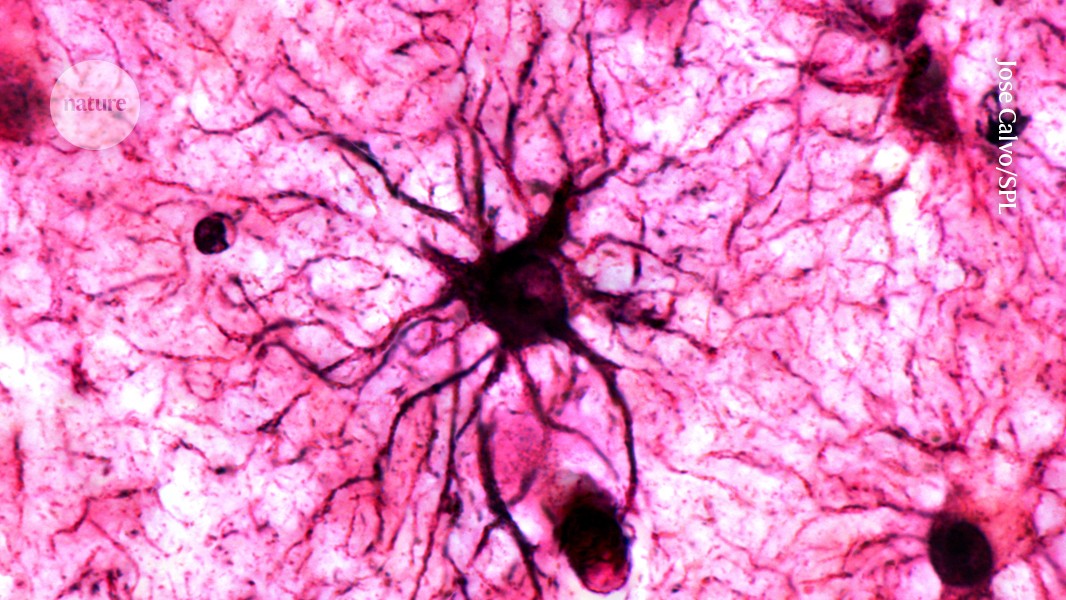

These cells could be a fresh target for treating Alzheimer's disease and memory conditions associated with PTSD go.nature.com/3W7aro4